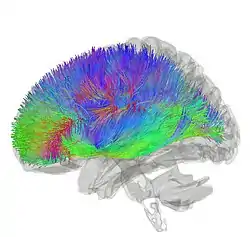

Tractography showing corticostriatal connections